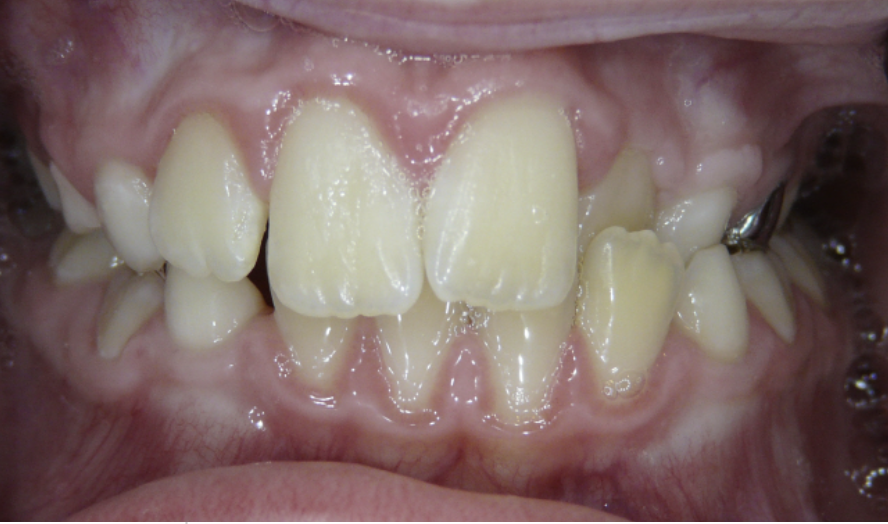

Crowding

Lack of space causes crowding as teeth erupt.